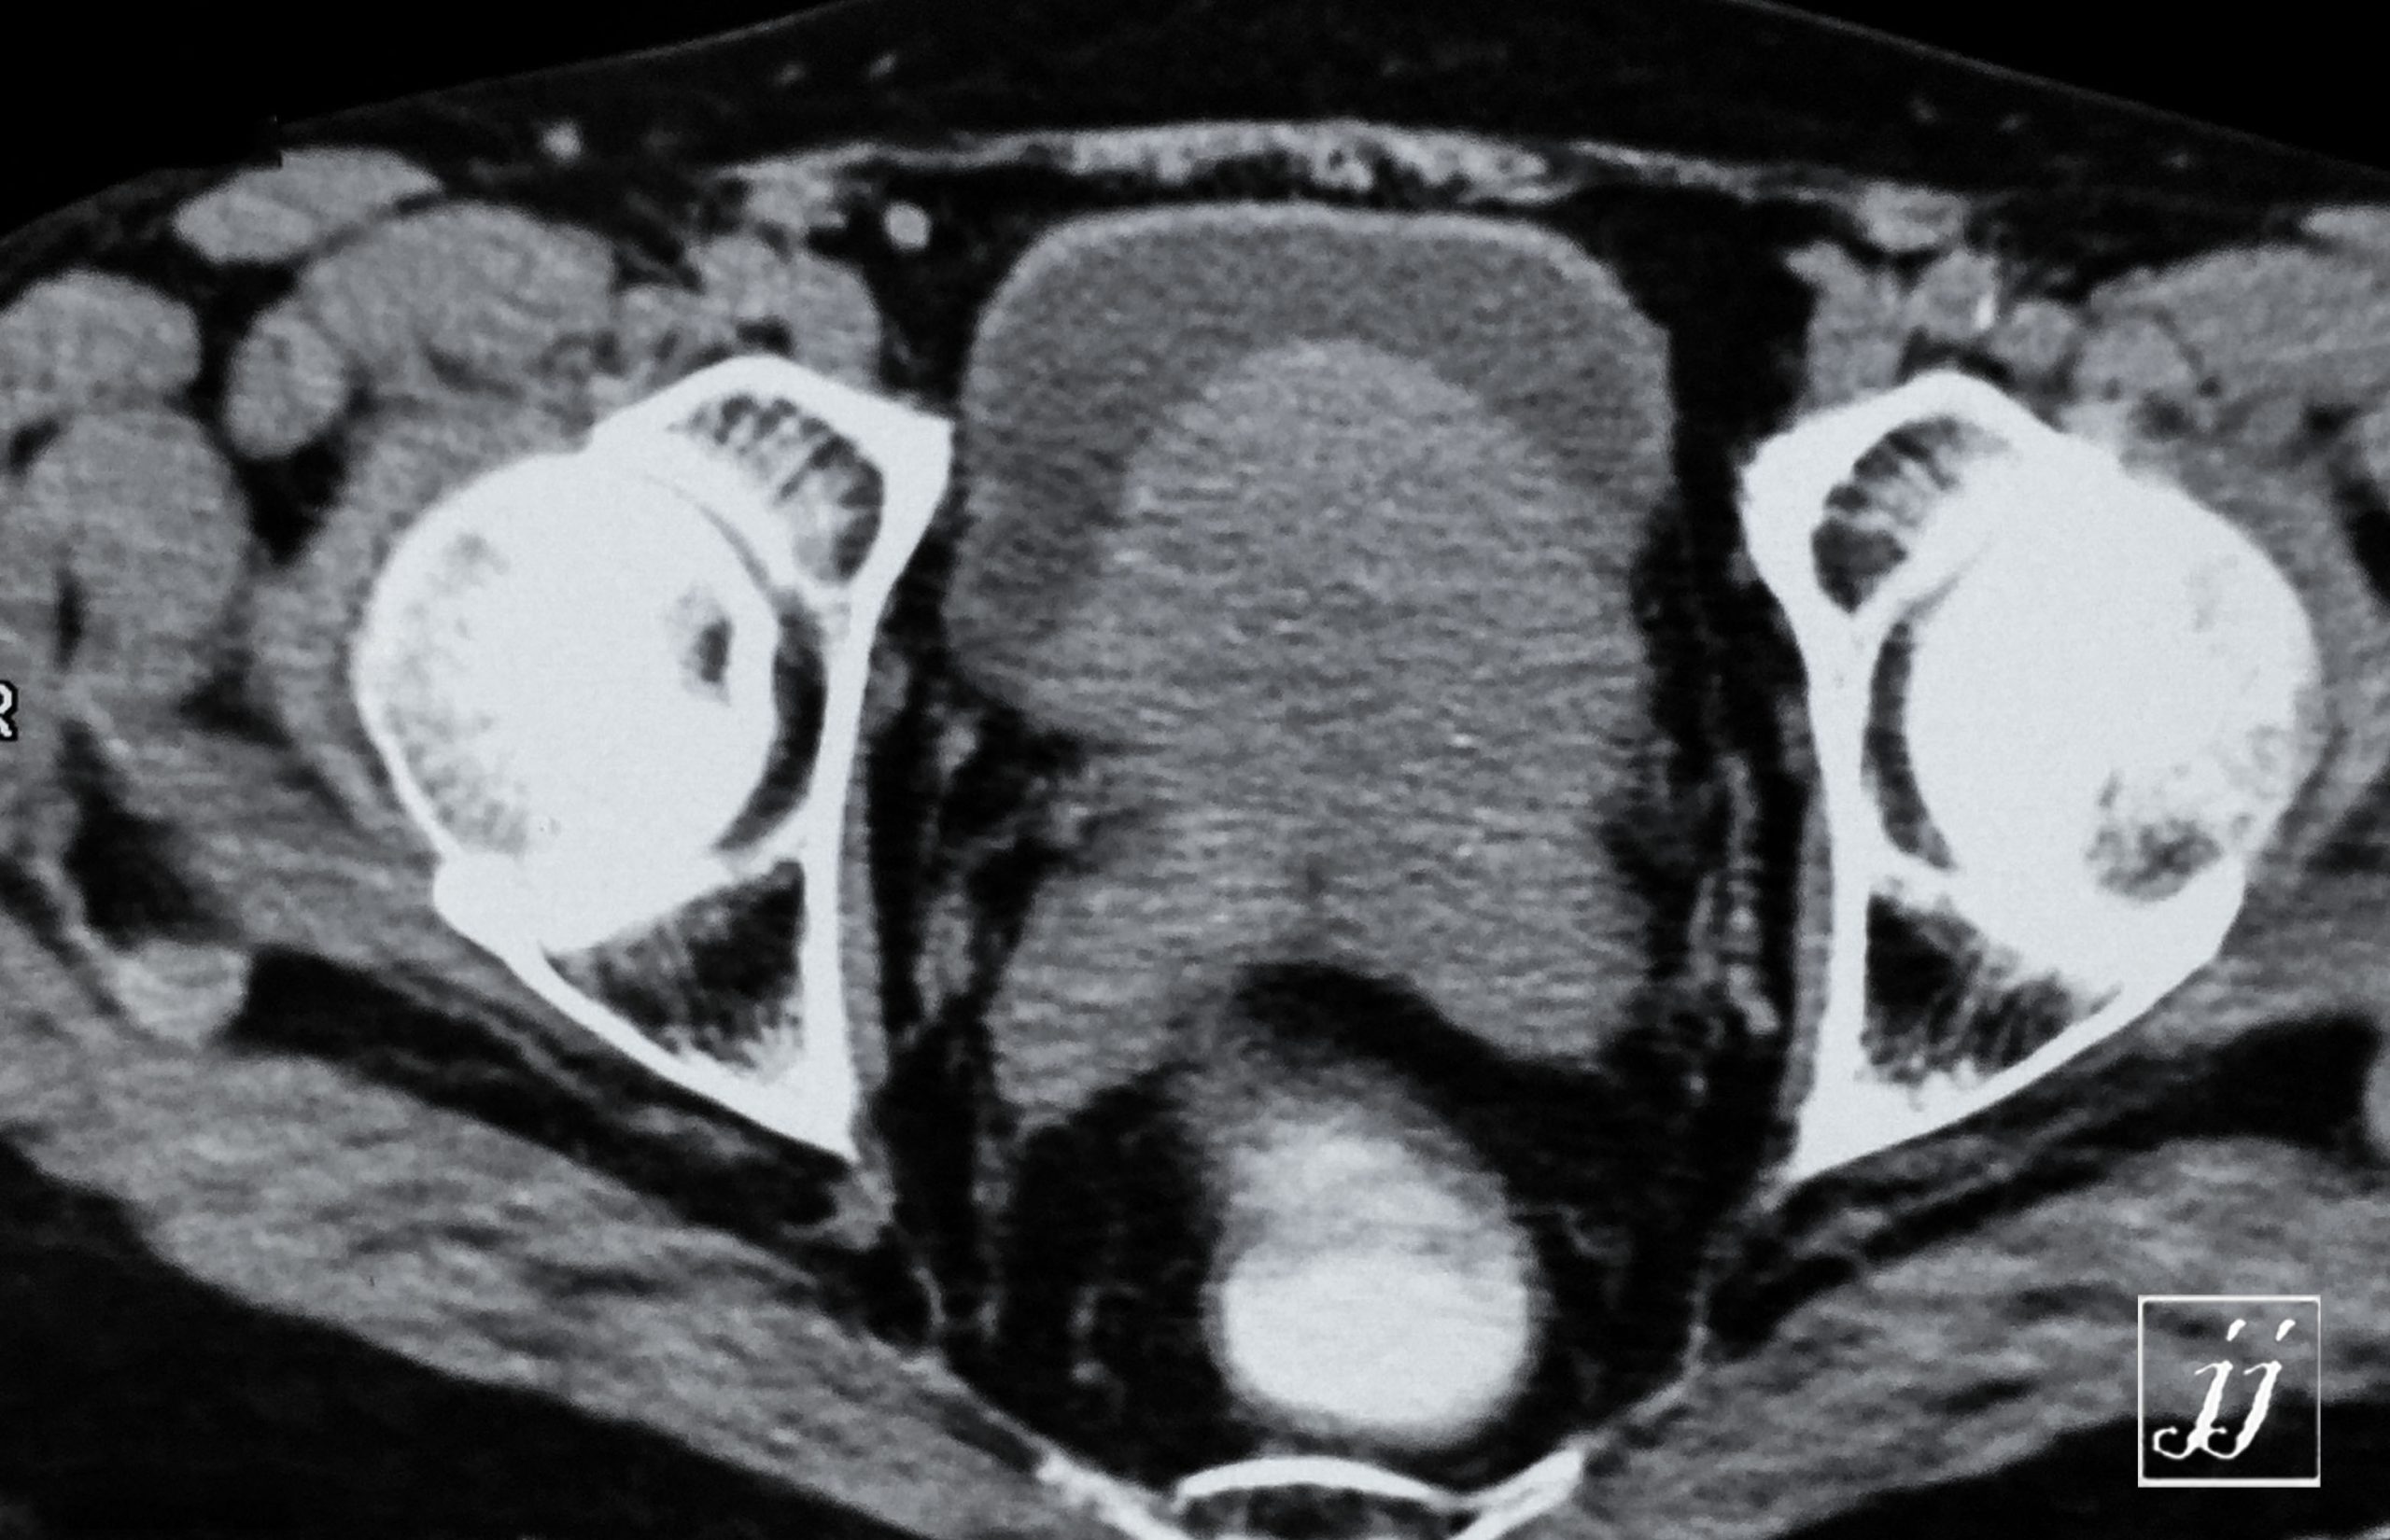

Abdomen- large prostate (2)